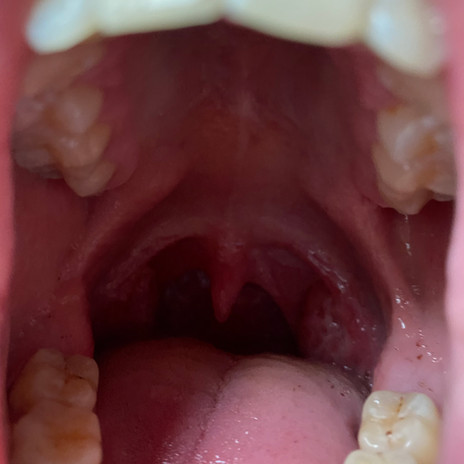

#uvula